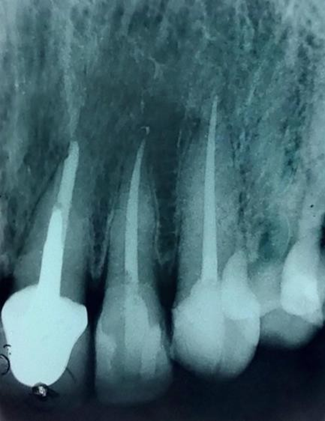

Após realização da odontometria eletrônica, o comprimento real de trabalho (CRT) foi determinado O preparo foi realizado com Protaper Ultimate Slider (16.02) e a Shaper (20.04) no comprimento real do dente com irrigação abundante de Hipoclorito de Sódio a 2,5%. As limas F1-F2-F3 e FX (35.12), esse denominado instrumento memória. (Figuras 2 e 3)

Figura 2 – Protaper Ultimate Slider (16.02) e a Shaper (20.04) no comprimento real do dente, e F1 no comprimento d de trabalho

Figura 3 – Instrumento memória a lima e FX (35.12) no comprimento d de trabalho.